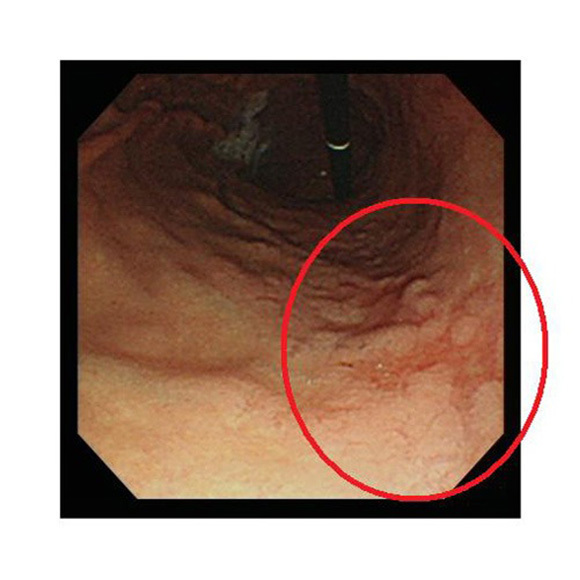

NBI:狭帯域光法システムで光を照らして観察します

NBI

食道・胃・大腸内の様子を明確に画像表示し、より癌を見つけやすくなりました。